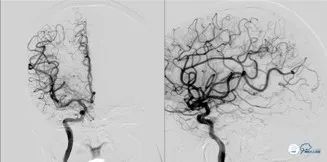

入院急查全脑血管造影术:可见基底动脉高密度征。

可见基底动脉尖端部血栓,呈次全闭塞状态,前向血流Mtici 2*级A**,无明显前循环向后循环代偿。